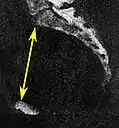

| Transverse diameter | Extends across the greatest width of the superior aperture, from the middle of the brim on one side to the same point on the opposite; | about 135 mm. |

Conjugata vera as measured on sagittal MRI Low-dose CT scan of the transverse diameter of the pelvic inlet, as part of pelvimetry

Low-dose CT scan of the transverse diameter of the pelvic inlet, as part of pelvimetry Obstetric conjugate, as a measure of the pelvic inlet in the sagittal plane